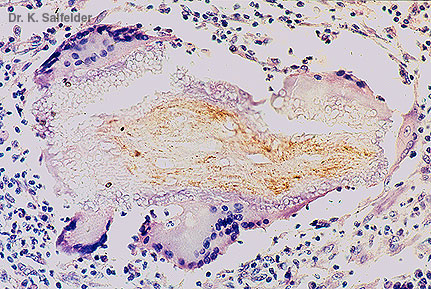

Abb. 16,47: Myzetome

Riesenzellen phagozytieren Reste einer Haarwurzel.HE-Faerbung